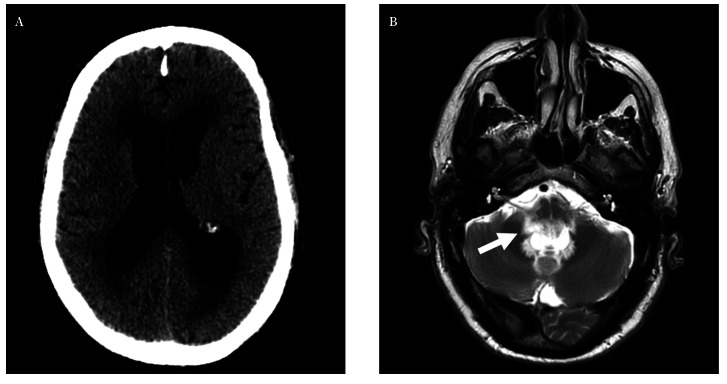

隐球菌脑膜炎是一种不常见的感染,发病率和死亡率都很高。在免疫功能正常的患者中发病十分罕见。我们介绍了一例 67 岁男性患者的病例,他因步态障碍和尿失禁的亚急性症状入院。神经系统检查显示他无法站立,记忆力受损。头颅造影显示梗阻性四室脑积水,小脑脚有神经胶质增生区域。对脑积水进行了内窥镜治疗,并采集了脑脊液样本,结果显示有新生隐球菌生长。经过内窥镜治疗,并使用两性霉素 B 脂质体和氟康唑进行为期十周的静脉抗真菌治疗后,患者病情有所好转。抗真菌药物可用于治疗免疫功能正常患者的隐球菌性脑膜炎。在极少数情况下,它会出现脑积水,这种情况需要使用脑脊液引流或内窥镜技术进行手术治疗。

Cryptococcal meningitis is an infrequent infection with high morbidity and mortality. Its presentation in immunocompetent patients is rare. We present the case of a 67-year-old male who was admitted for subacute symptoms of gait disturbance and urinary incontinence. Neurological examination revealed inability to stand and memory impairment. Cranial imaging showed obstructive tetraventricular hydrocephalus with areas of gliosis in the cerebellar peduncles. Endoscopic treatment of hydrocephalus was performed and cerebrospinal fluid samples taken revealing the growth of Cryptococcus neoformans. The patient improved with the endoscopic treatment and after completing intravenous antifungal therapy with liposomal amphotericin B and fluconazole for ten weeks. Antifungals are used to treat cryptococcal meningitis in immunocompetent patients. On rare occasions, it presents with hydrocephalus, a situation that requires surgical treatment using cerebrospinal fluid diversions or endoscopic techniques.